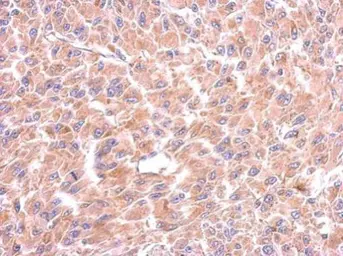

Anti-Tryptophanyl tRNA synthetase antibody used in IHC (Paraffin sections) (IHC-P). GTX110223

GTX110223 IHC-P Image

Immunohistochemical analysis of paraffin-embedded U87 xenograft, using Tryptophanyl tRNA synthetase(GTX110223) antibody at 1:500 dilution.

Antigen Retrieval: Trilogy™ (EDTA based, pH 8.0) buffer, 15min